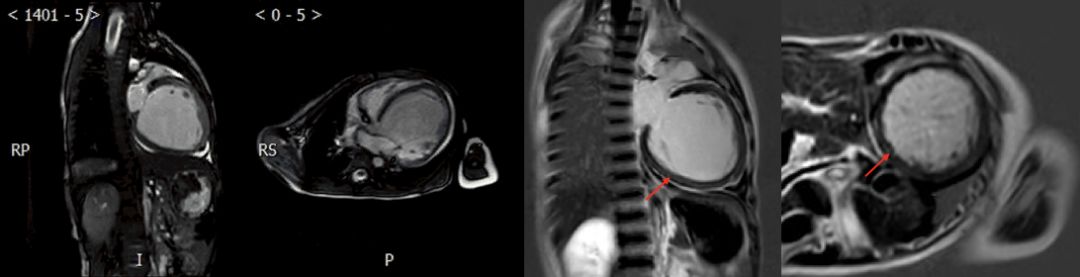

➤ 本病例3例患儿在初始评估后均行CMR检查

✦ Case 3

CMR:左心房前后径约50mm,右心房前后径约42cm,左心室舒张末期内径约43mm,右心室舒张末期内径约35mm,EF 71%

电影MRI:右心室外侧壁形态不规则。左心室及右心室室壁运动减低,舒张功能下降;心包略增厚,心包腔见液性信号影

复查CMR